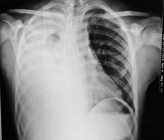

Se realizó radiografía de tórax observándose derrame masivo en campo pulmonar derecho.

Ante la sospecha de hidrotórax secundario a DP se realizó toracocentesis diagnóstica y terapéutica, drenándose 1600 ml de líquido claro, con características bioquímicas compatibles con líquido peritoneal. (Figura 1,Tabla 1).